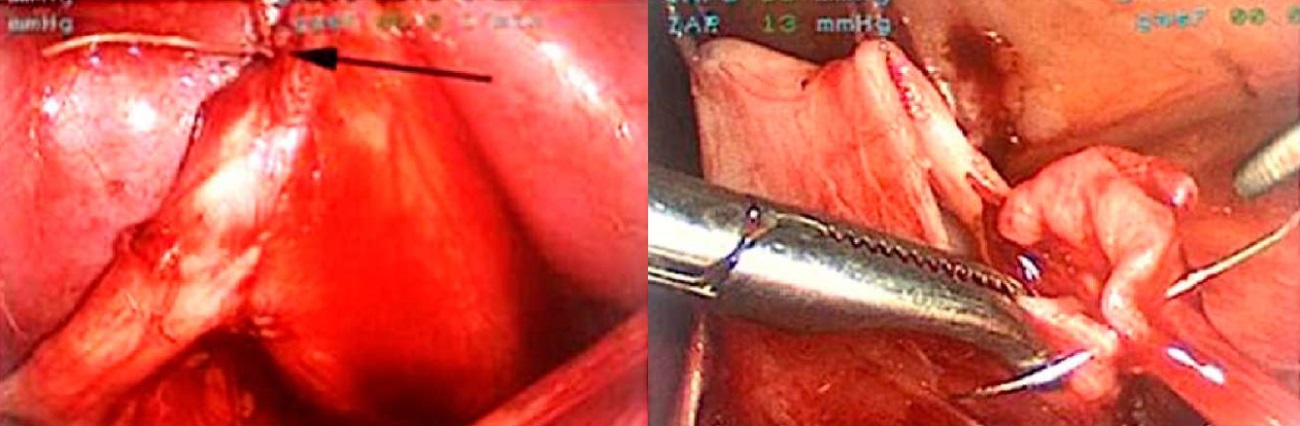

Введение. Обструкция пиелоуретерального сегмента (ОПУС) — самая частая причина хирургических вмешательств на верхних мочевых путях у детей. Нами проведён сравнительный анализ результатов применения робот-ассистированной лапароскопической пиелопластики (РАП) с использованием системы da Vinci Xi и традиционной лапароскопической пиелопластики (ЛП).

Материалы и методы. В исследование включены 40 пациентов, которым выполнена пиелопластика. Мы разделили пациентов на две группы: в группе 1 — 20 пациентов, которым выполнена РАП, в группе 2 — 20 пациентов, которым выполнена ЛП. Все операции выполнены одним хирургом.

Заключение. Сравнительный анализ эффективности и безопасности использования РАП и ЛП при ОПУС у детей демонстрирует сопоставимые результаты по длительности хирургии и динамике регрессии дилатации чашечно-лоханочной системы в послеоперационном периоде. В качестве преимущества РАП по сравнению с ЛП следует считать сохранение физических кондиций оператора на всём протяжении формирования анастомоза, позволяющих формировать анастомоз максимально прецизионно, избегая компромисса между желаемым качеством наложения интракорпорального шва и реальным результатом на фоне неизбежной физической усталости оператора при использовании лапароскопического доступа.